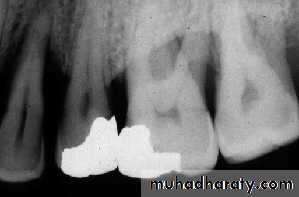

Subgingival calculus that appears as irregular radiopaque projections in the maxillary anterior region.

Calculus that appears as sharp, pointed radiopacities along the surfaces of mandibular anterior teeth.